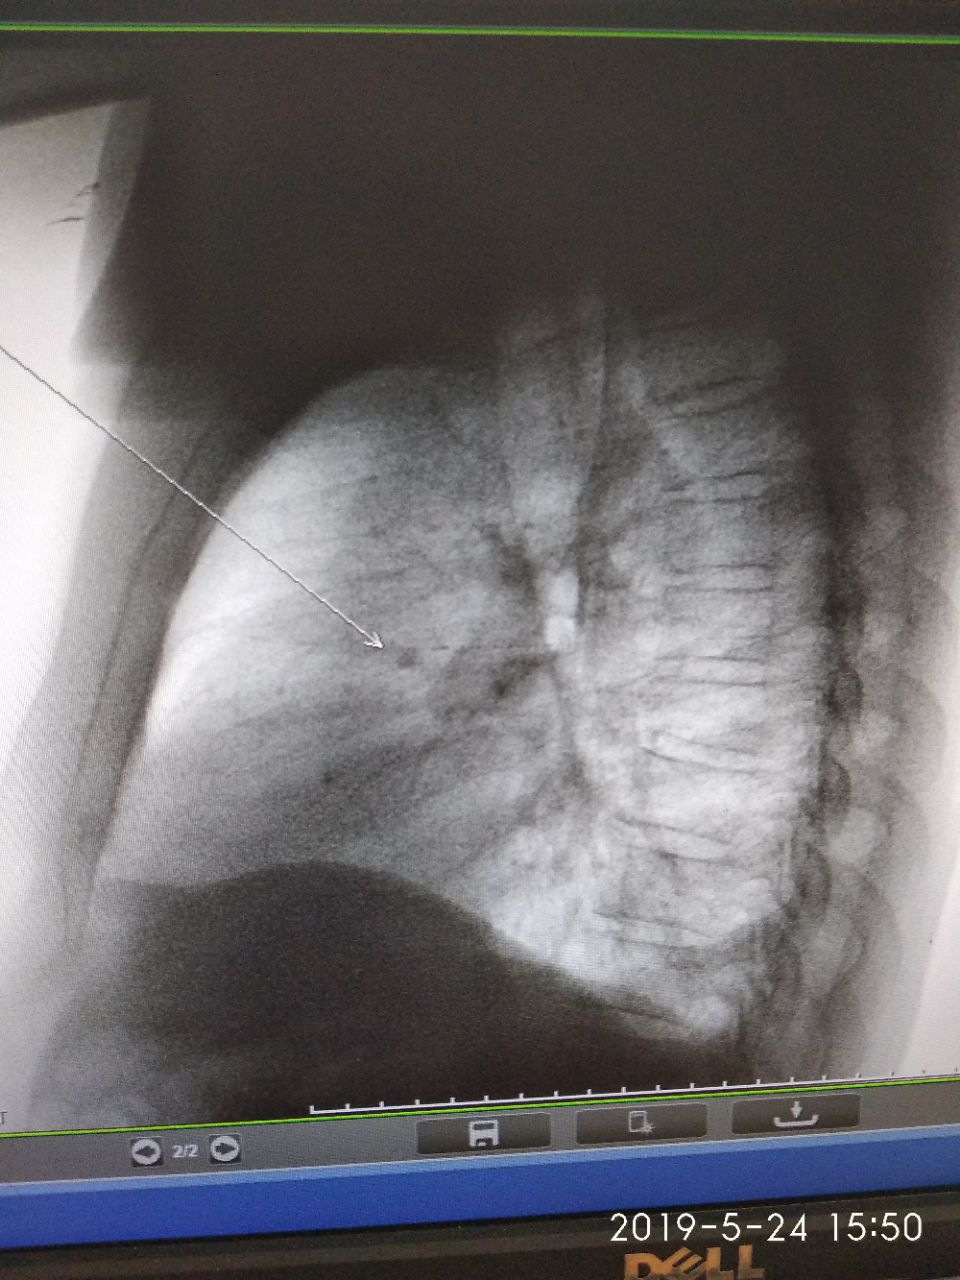

Доброе утро,не могу полностью весь снимок снять,жёсткий получился.Женщина 1937 г с онкологией.Подскажите,про релаксацию диафрагмы и бляшки плевральные что ли...

Что это в нижних отделах ?

Обызвествления хрящевой части рёбер

Главное чтоб в легочной паренхиме чисто было. ) обычно с жесткими снимками больше костные структуры прорабатываются